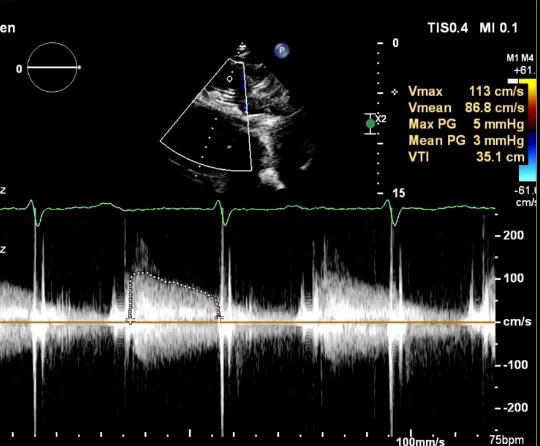

三尖瓣瓣中瓣术后平均压差3mmHg

3.经股静脉入路送入16F E-sheath可扩张导管鞘,随后送入SAPIEN 3球扩瓣1输送系统,由于肺动脉入路朝上走,无需调弯,顺利跨瓣,将SAPIEN 3球扩瓣送入预定位置。精准定位后,以160次/分快速起搏,并保证1:1完全夺获,缓慢释放瓣膜。术后超声检查结果显示即刻跨瓣压差从术前9mmHg降至3mmHg,顺利完成瓣膜释放,回撤导管、导丝。